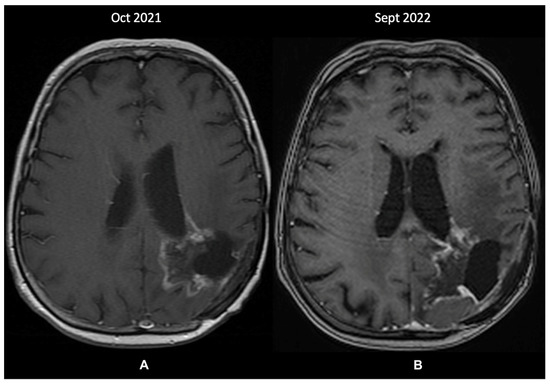

2.1. A Case of Grade 2 Diffuse Astrocytoma Upstaged to Glioblastoma

2.2. A Case of Glioblastoma Downstaged Due to the IDH Status